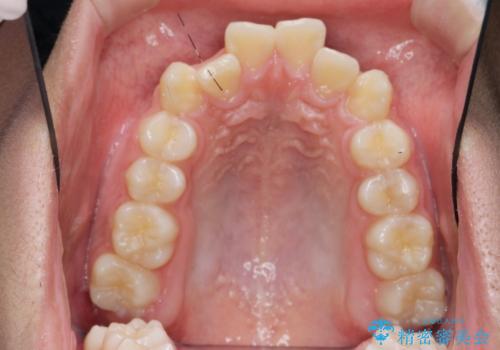

- 前歯のがたつきが原因で歯ブラシしづらい、見た目を改善したい!と矯正治療を希望され来院されました。

スペースの不足が見られるため、小臼歯の4本抜歯を行いマルチブラケットを用いた矯正治療を計画します。

噛み締めが強く、治療に時間がかかりましたが矯正治療の仕上がりに満足いただくことができました。